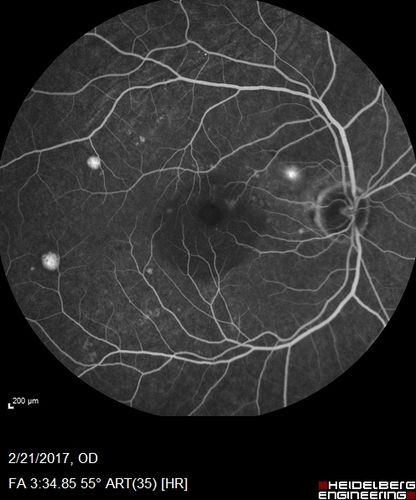

Multifocal Bilateral Central Serous Retinopathy in African American Male

67 year old african american male with : Blurred Vision OD. Duration of Problem: 4-6 weeks. VA 20/32 OD 20/20 OS